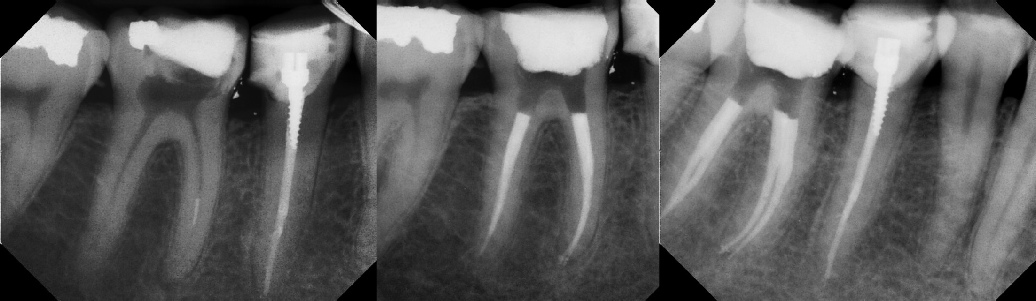

COMPLICATED ANATOMY LARGE LESIONS CALCIFIED CANALS PERFORATION / RESORPTION SEPARATED INSTRUMENTS SURGICAL CASES RETREATMENT / pOST REMOVAL OPEN APICES ACCESS THRU CROWNS Root Canal Case Portfolio

Pre-op Post-op 1 Post-op 2